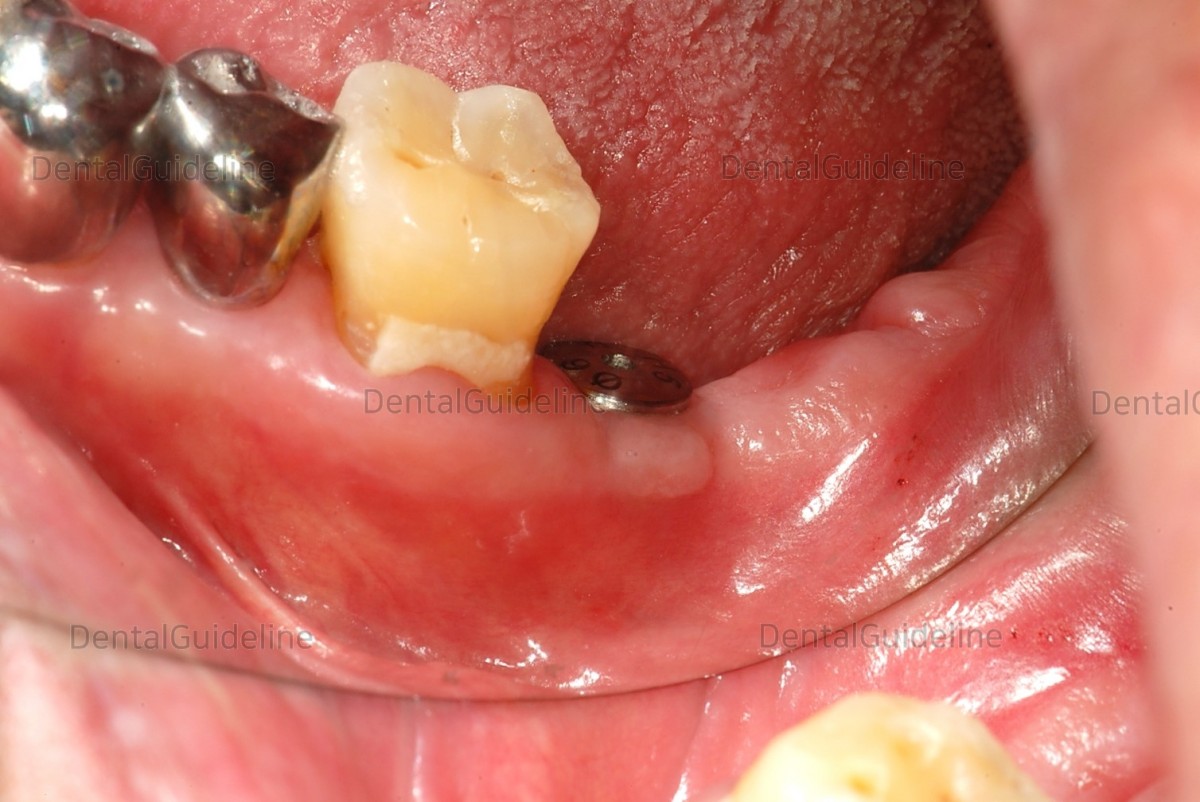

14 days after the surgery